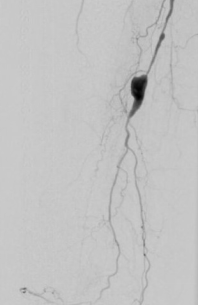

7. 术后造影血流恢复

本例患者股浅动脉重度闭塞,股浅远端重度钙化病变近收肌管,利用Shockwave冲击波球囊获得满意的管腔准备后联合使用DES,为保障远期通畅植入支架,支架膨胀形态理想。

我国患者股浅动脉又多以长段闭塞病变为主,为保障远期通畅率,支架的植入往往不可避免,此时如何优化支架膨胀则至关重要。利用“聚焦式”的冲击波能量作用于重度钙化环最薄弱处,在低压下安全打开钙化斑块,尤其是限制血管床弹性的环形钙化,可有效增加管腔顺应性,减少弹性回缩。